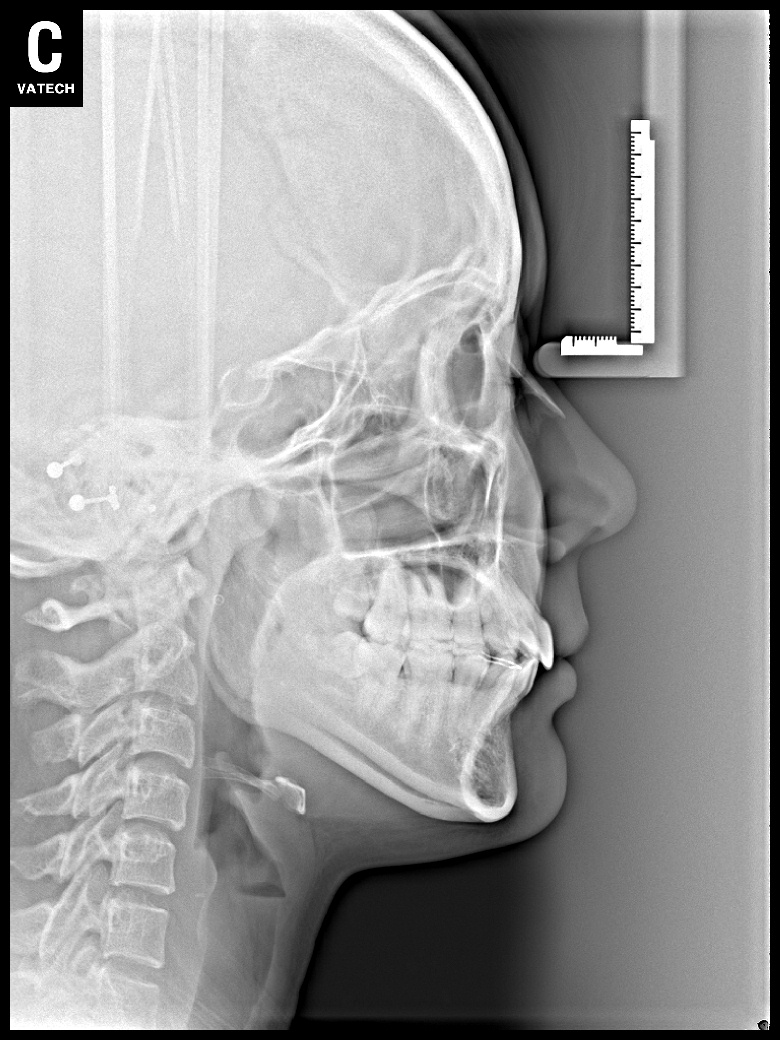

치료 전 사진입니다.